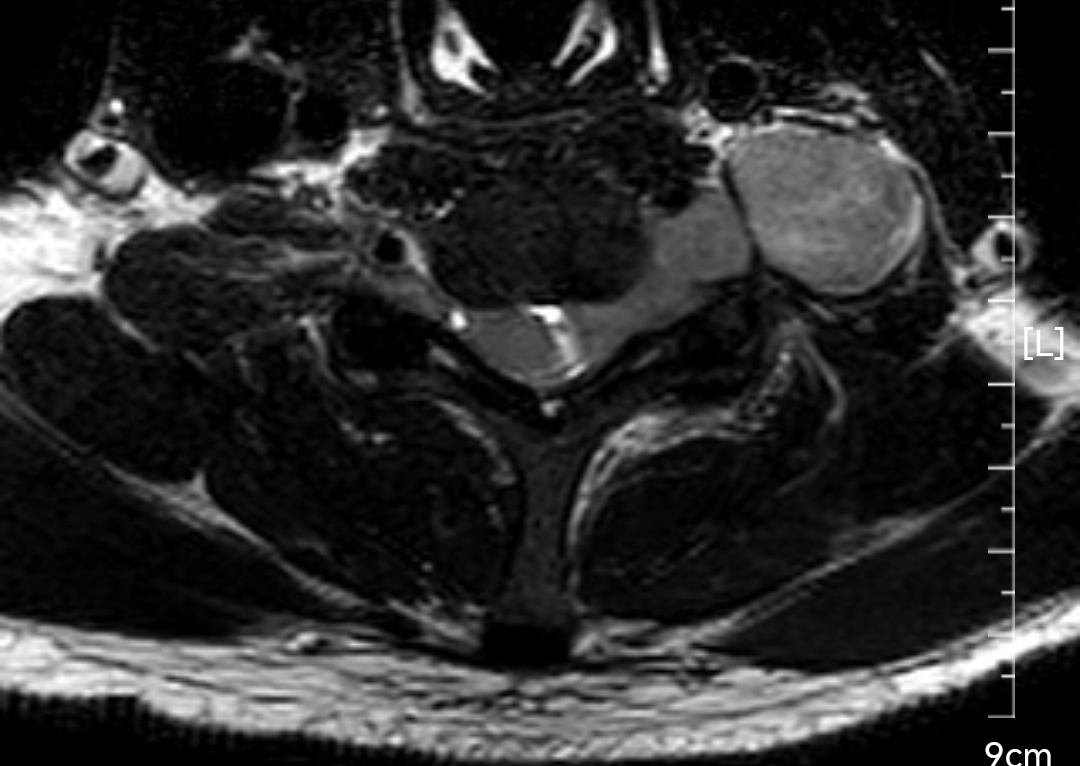

颈椎哑铃型神经纤维瘤,椎间孔汇合,安全又便于操作~